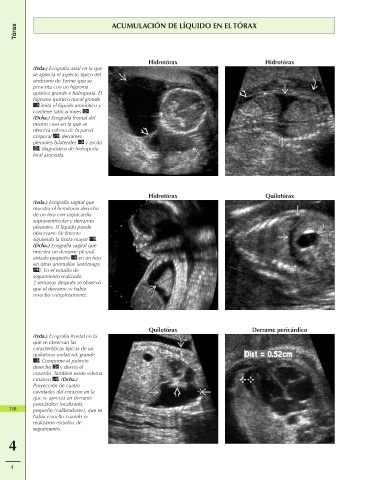

Tórax ACUMULACIÓN DE LÍQUIDO EN EL TÓRAX

Hidrotórax Hidrotórax

(Izda.) Ecografía axial en la que

se aprecia el aspecto típico del

síndrome de Turner que se

presenta con un higroma

quístico grande e hidropesía. El

higroma quístico nucal grande

imita el líquido amniótico y

contiene tabicaciones .

(Dcha.) Ecografía frontal del

mismo caso en la que se

observa edema de la pared

corporal , derrames

pleurales bilaterales y ascitis

, diagnóstico de hidropesía

fetal asociada.

Hidrotórax Quilotórax

(Izda.) Ecografía sagital que

muestra el hemitórax derecho

de un feto con taquicardia

supraventricular y derrames

pleurales. El líquido puede

observarse fácilmente

siguiendo la fisura mayor .

(Dcha.) Ecografía sagital que

muestra un derrame pleural

aislado pequeño en un feto

sin otras anomalías (estómago

). En el estudio de

seguimiento realizado

2 semanas después se observó

que el derrame se había

resuelto completamente.

Quilotórax Derrame pericárdico

(Izda.) Ecografía frontal en la

que se observan las

características típicas de un

quilotórax unilateral, grande

. Comprime el pulmón

derecho y desvía el

corazón. También existe edema

cutáneo . (Dcha.)

Proyección de cuatro

cavidades del corazón en la

que se aprecia un derrame

pericárdico localizado,

158 pequeño (calibradores), que se

había resuelto cuando se

realizaron estudios de

seguimiento.